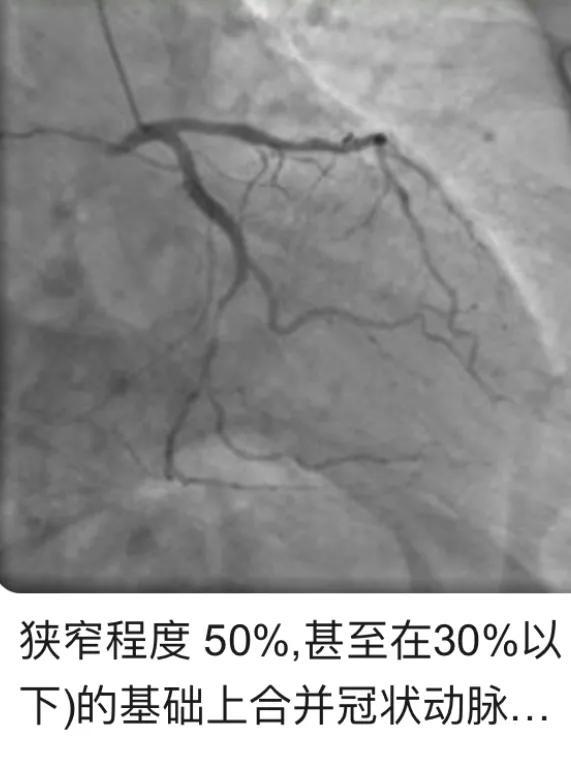

冠動脈疾患の診断のゴールドスタンダード:冠動脈疾患は冠動脈造影によって診断することができ、左冠動脈主幹動脈、左冠動脈前下行枝、左冠動脈回旋枝、右冠動脈のいずれか1つ以上の狭窄が50%以上であることが明らかになる。

50%未満の狭窄によるアテローム性動脈硬化症の冠動脈造影の結果は、冠状動脈性心臓病と呼ばれることはできません、唯一の冠状動脈のアテローム性動脈硬化病変と呼ばれることができます。一般的な医師の50%以上の冠動脈狭窄は、低比重リポタンパクコレステロールLDLを作る薬が50%以上低下した場合、スタチン系薬剤の処方を与えるだけでなく、プラークがもはや "狂気の成長 "より安定し、破裂し、心筋梗塞を誘発する可能性が低くなるように、プラーク内のコア脂質のために、LDLLDLは、プラーク中のコア脂質の主成分は、元の値の50%以上有意に低下し、さらにプラークを小さくし、逆に、元の狭窄が50%よりも軽度である場合、プラークの機械化の狭窄のために、狭窄が50%未満になり、その後、冠状動脈性心臓病の帽子を置くことができないことがあります。これは今でもしばしば臨床で見られることである。